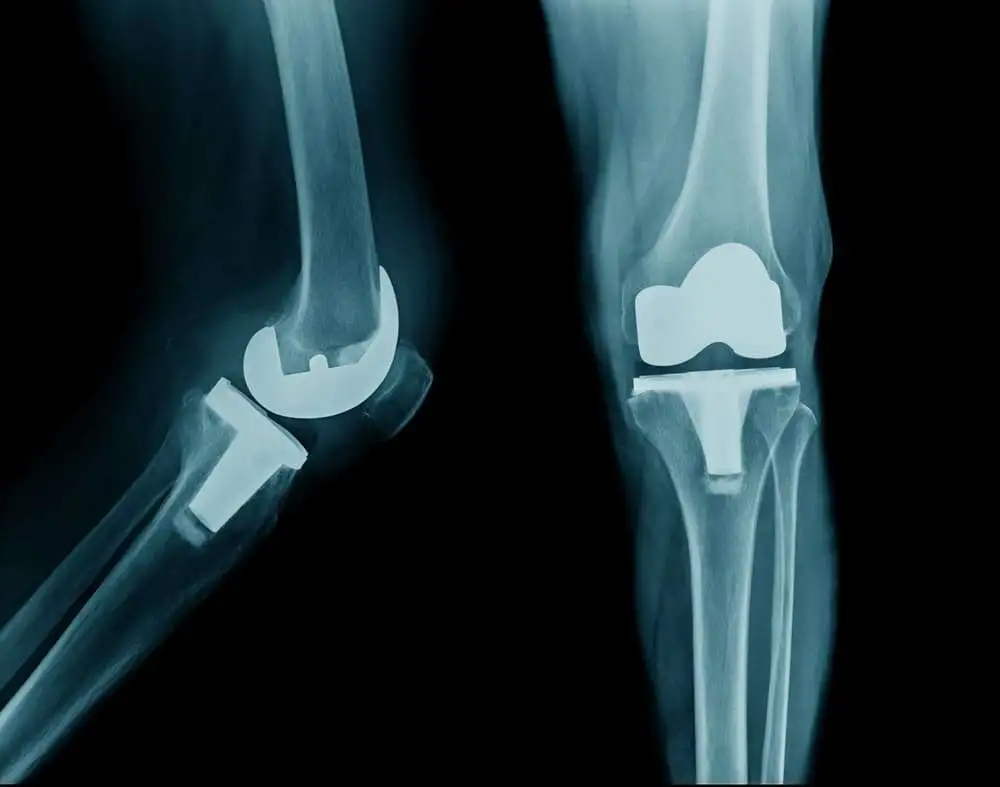

В образцах цельных хрящей, коллагенного и неколлагенового компонентов хрящей, собранных во время эндопротезирования сустава, было измерено содержание D- и L-аспартата (Асп). Для каждого из компонентов было рассчитано отношение рацемизации Асп (Асп-ОР = D/D + L-Асп), которое дает представление о доле старого белка в общем содержании белка.